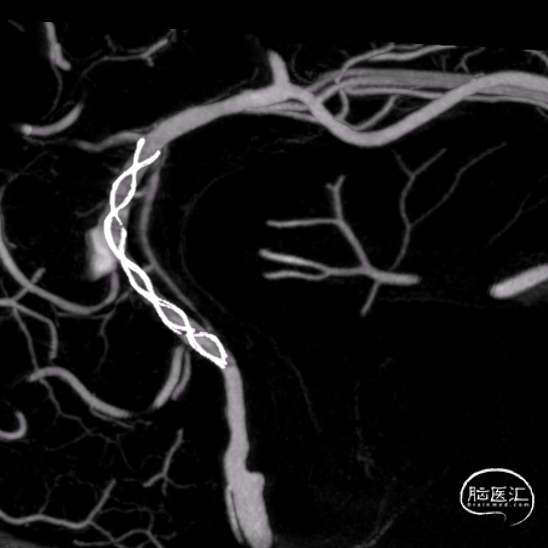

术后VASO CT。

强易达(Choydar)血流导向密网支架材质是镍钛合金,输送易到位;头端导丝、50%释放点、100%释放点清晰,便于观察支架位置。

50%Mark点可帮助分析后半段打开后的尾端位置,近端血管较粗考虑支架短缩,也可调整支架的50%Mark点置于偏近端一些。

支架由2对4根铂钨合金显影丝以对向排列的方式,混合编入支架主体,呈3D立体显影效果,便于观察支架贴壁情况。